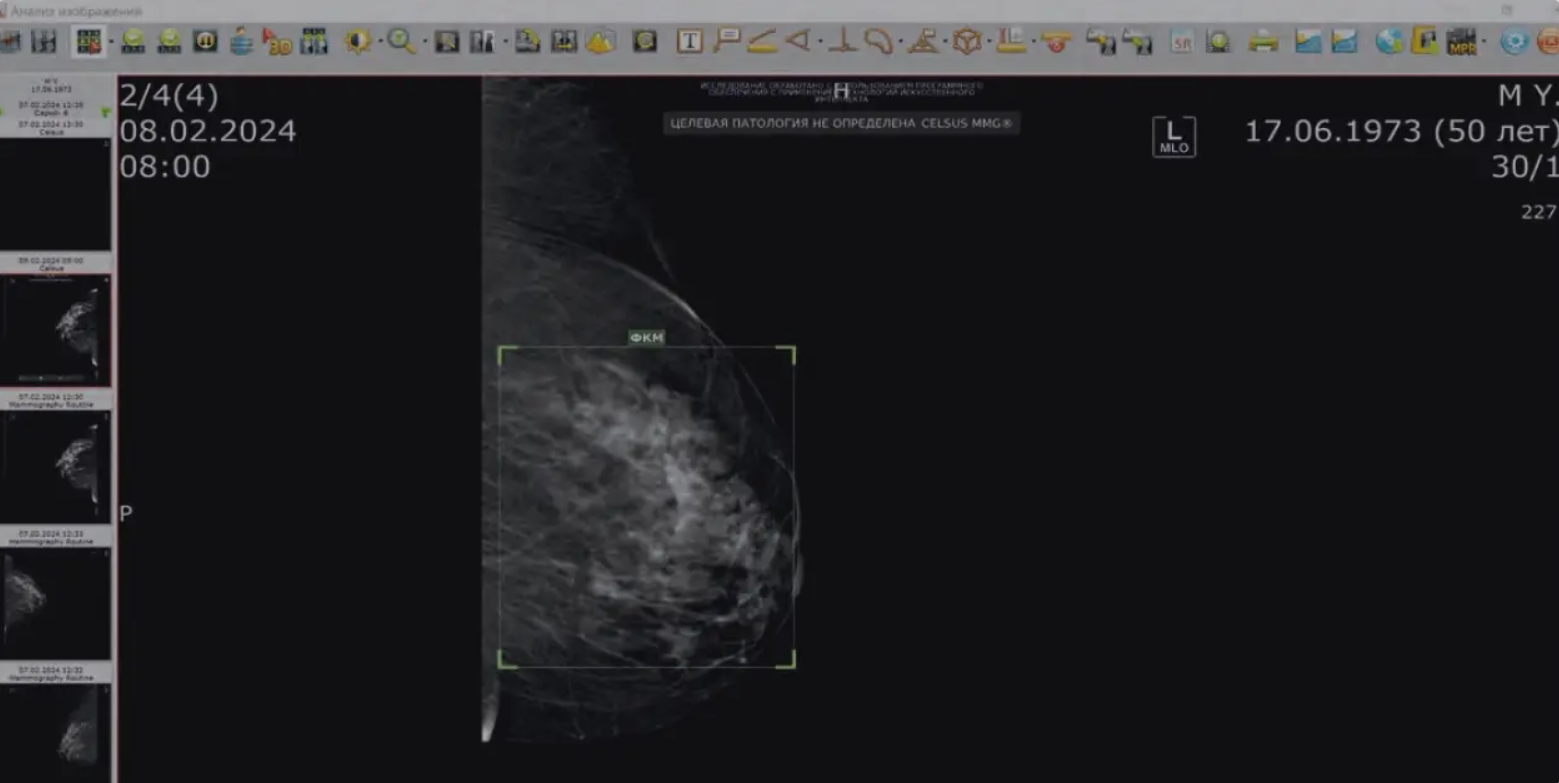

ИНТЕРФЕЙС СТАНЦИИ ОБРАБОТКИ ИЗОБЖЕНИЙ

Система детектирует и выделяет на изображении 11 классов объектов.

Пакет данных из 4 проекций ВСС, 1СС, ВМЕО, ЕМГО обрабатывается менее 60 секунд.

Точность интерпритации снимков по ВI-RADS более 95%.

Система определяет плотность ткани молочной железы по АСВ и присваивает исследованию категорию ВI-RADS.

Руководители медицинских учреждений могут анализировать диагностику по шкале ВI-RADS и сравнивать решения врачей с результатами искусственного интеллекта, что снижает вероятность ложноположительных и ложноотрицательных результатов.

Наша станция врача предлагает автоматическое описание медицинских снимков, что ускоряет получение заключений и минимизирует ошибки, связанные с человеческим фактором.,